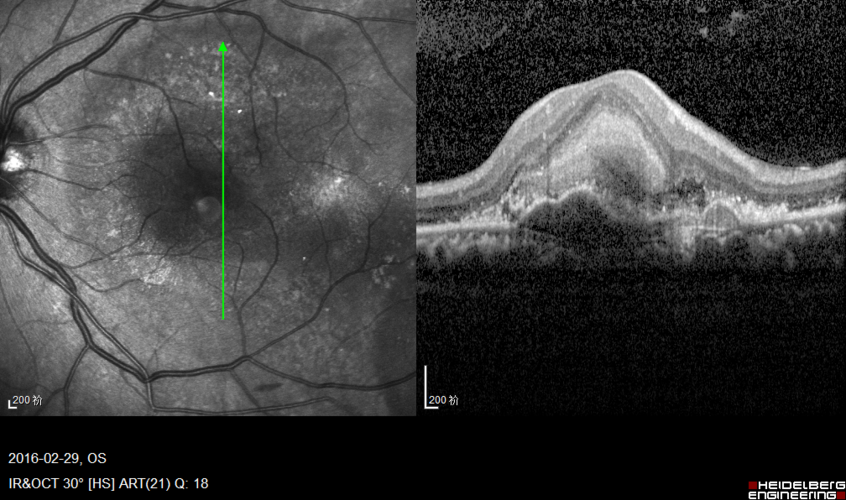

干性黄斑变性oct图片

干性黄斑变性oct图片,黄斑变性oct图片

黄斑变性oct图片

老年性黄斑变性oct图片

湿性老年黄斑变性oct

黄斑变性oct

黄斑变性OCT读图

老年性黄斑变性OCT